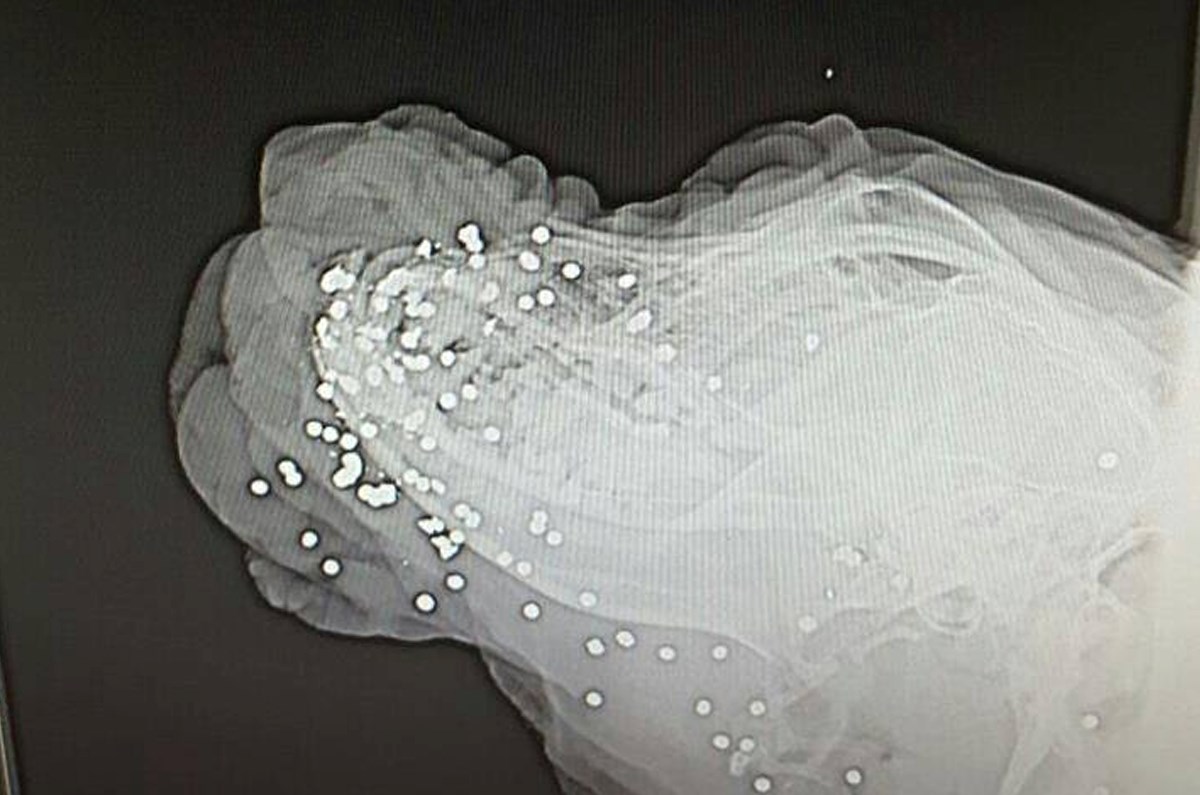

Oprez!!! Psihopat u Zemuniku pucao psu u glavu sačmaricom!

http://www.antenazadar.hr/clanak/2016/04/u-zemuniku-psu-raznijeli-njusku/